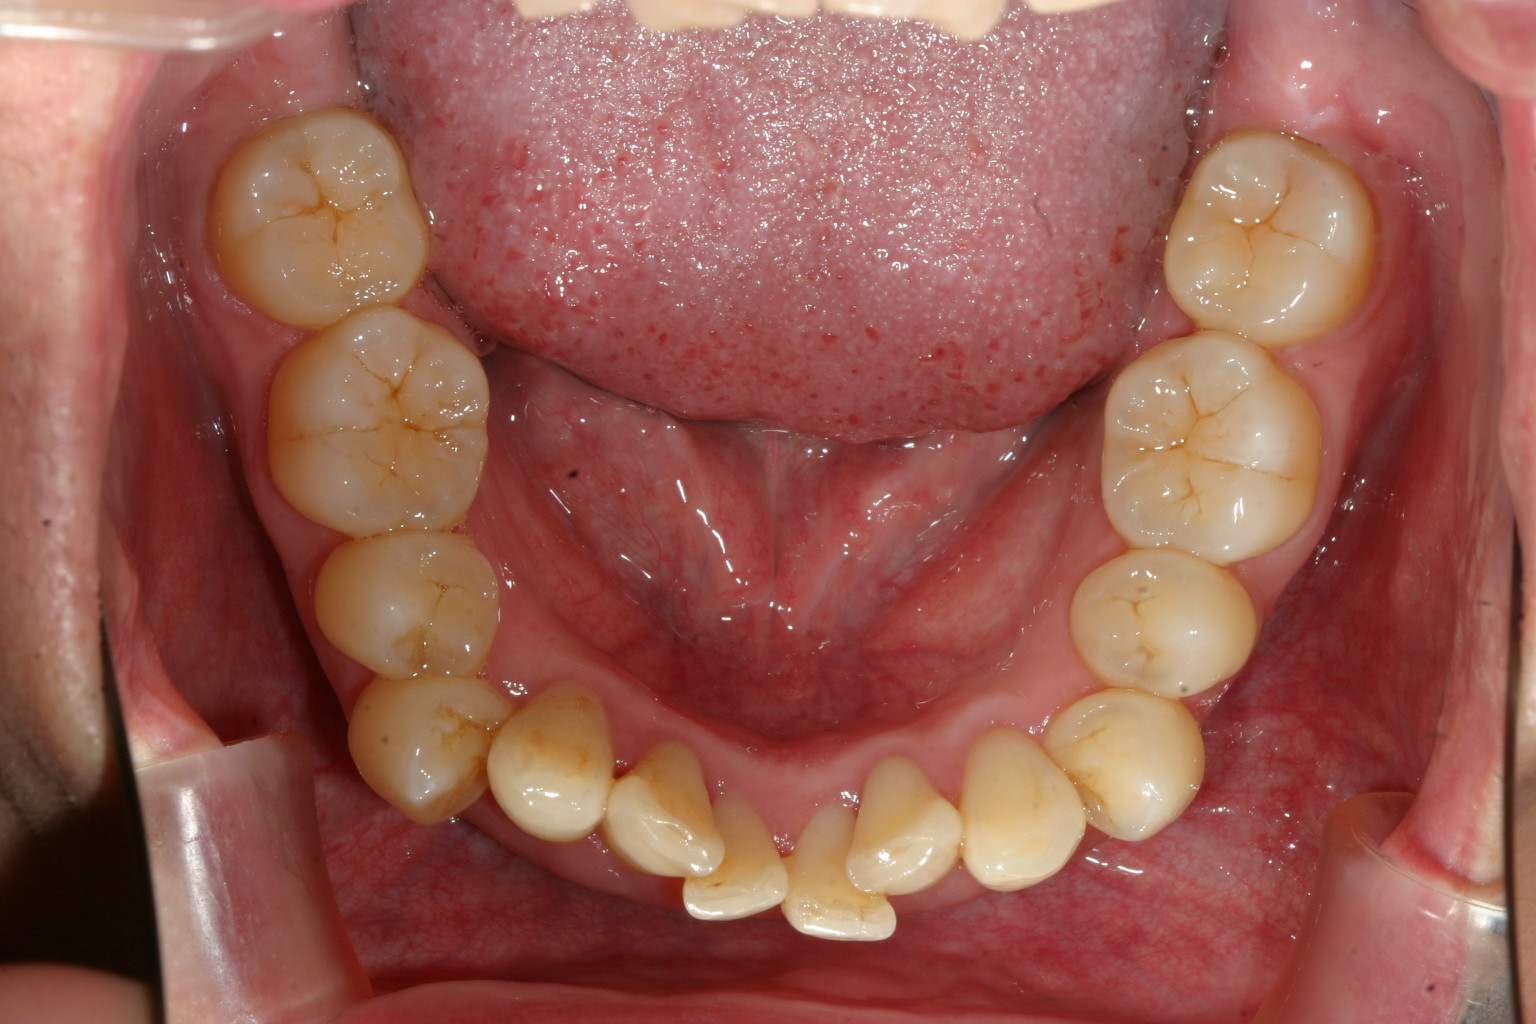

下顎の歯もガタガタになってます。

下顎のガタガタも綺麗に改善してます。